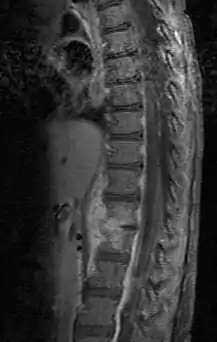

| Discitis in a 2 year old child. | |

Discitis, or diskitis, is an infection in the intervertebral disc space that affects different age groups. In adults, it can lead to severe consequences, such as sepsis or epidural abscess, but it can also spontaneously resolve, especially in children under 8 years of age. Discitis occurs post-surgically in approximately 1–2 percent of patients after spinal surgery.